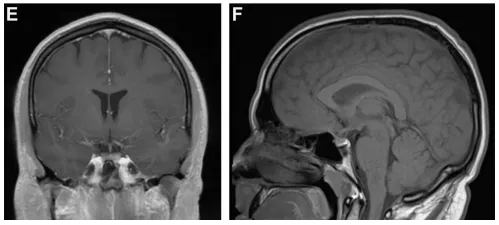

令人惊讶的是,4周后复查MRI显示,之前那个占位病变居然接近完全消失了(图1E、1F)。我以为这场风波就此结束,之后也没有继续随访。

(E、F)4周后随访MRI冠状位及矢状位扫描显示原蝶骨平台及鞍上占位病变接近完全消失。